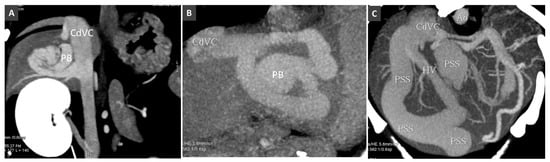

3.4. Portal Vein Thrombosis

3.8. Porto-Portal Collaterals or Cavernous Transformation of the Portal Vein

- Specchi, S.; Pey, P.; Ledda, G.; Lustgarten, M.; Thrall, D.; Bertolini, G. Computed tomographic and ultrasonographic characteristics of cavernous transformation of the obstructed portal vein in small animals. Vet. Radiol. Ultrasound 2015, 56, 511–519. [Google Scholar] [CrossRef] [PubMed]